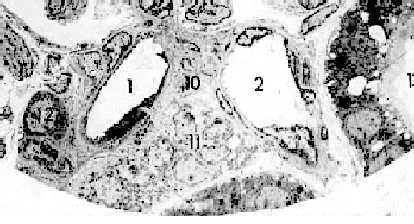

| Электронная микрофотография - юкстагломерулярный аппарат. |

1. А здесь перед нами - нижняя часть снимка, приводившегося в п. 28.2.3.3.III. 2. Видны следующие структуры: приносящая (1) и выносящая (2) артериолы; | |

плотное пятно (тёмный участок в самом низу снимка); юкстагломерулярные клетки (12) - слой тёмных клеток в средней оболочке приносящей артериолы (аналогичные клетки содержатся, как мы знаем, и в выносящей артериоле, но на снимке практически не видны), и наконец, юкставаскулярные клетки (11) - скопление светлых клеток в треугольном пространстве между двумя артериолами и дистальным извитым канальцем. |